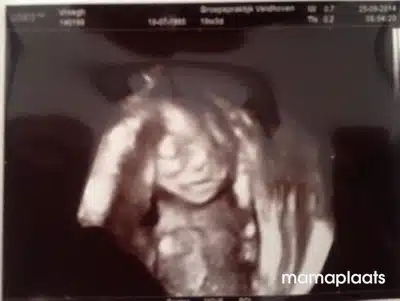

Het bewijs dat ik in verwachting was…